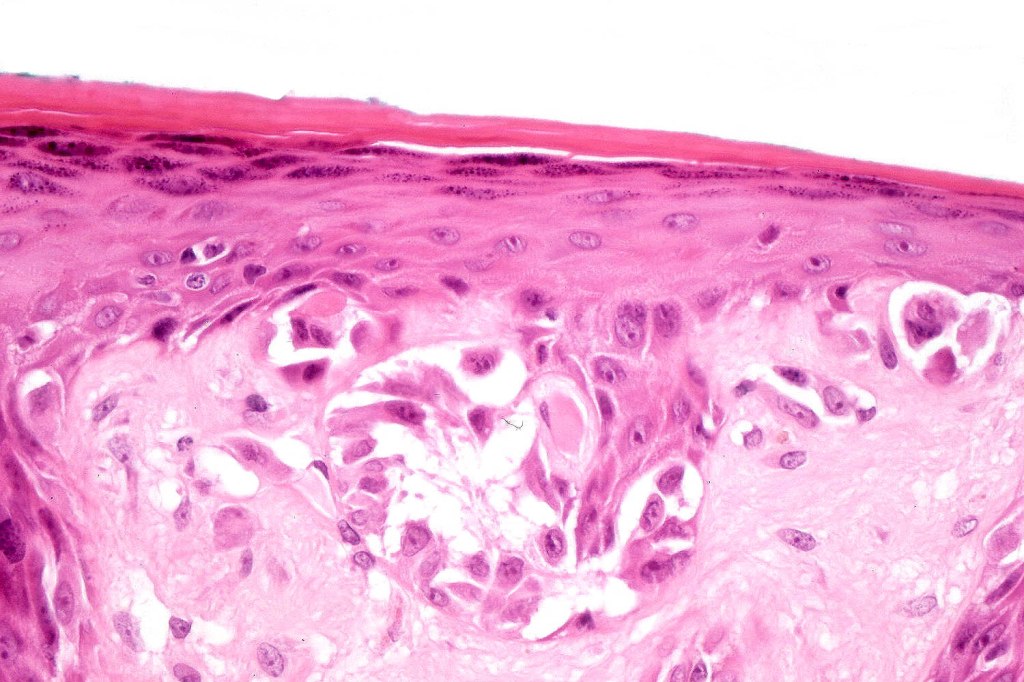

•Matures with depth-often best recognized at scanning/low power magnification & readily confirmed with S100 or MART1

•Maturation implies nest size and cell size diminishing with depth, at the base, the infiltrate may have a single cell infiltrating pattern

•Junctional nests often vertically orientated, dyscohesive with a surrounding retraction artifact

•Intracytoplasmic pseudoinclusions commonly present in epithelioid cells